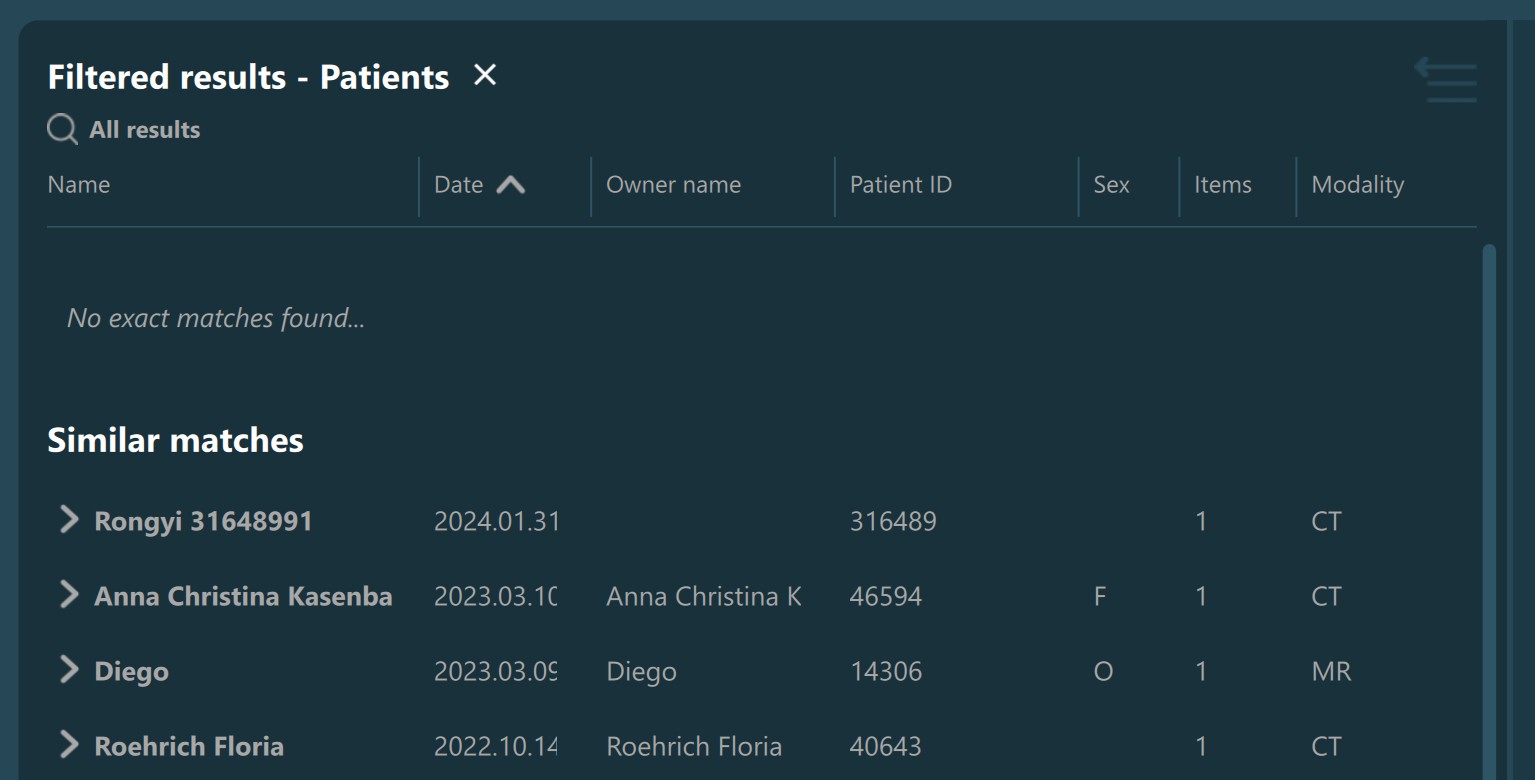

Patient name, Owner name, Patient ID: Use the input fields to specify the value of the following parameters. The Study List is automatically filtered after the initial filter timer has elapsed. When using these parameters, the studies in the Study List are separated into exact and similar matches.

Filtered Study List information with only similar matches found: